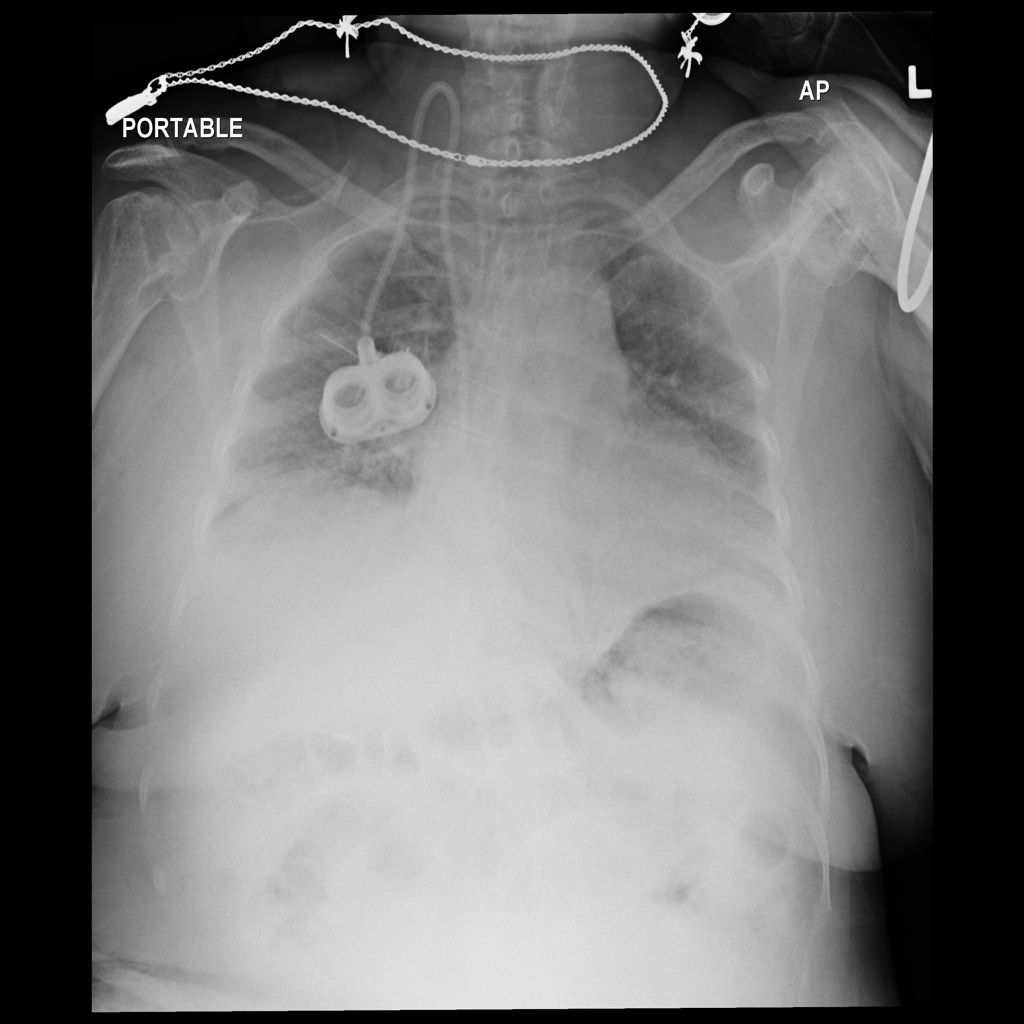

Showing up to 90 reference images for Nodule.

PAT-988D · IMG-001Nodule

PAT-988D · IMG-001

AP